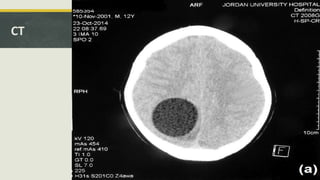

CT

• #16 well-defined CSF density lesion right parieto-occipital lobe hypodense with some mass effect on the midline which appears slightly bulging to the left (pushing the posterior interhemispheric fissure) effacement of the cortical sulci with minor compression of the posterior body of the right lateral ventricle, but no overt midline shift no significant perilesional hypo density on the adjacent brain parenchyma to suggest vasogenic edema at this particular cut there are no foci calcification at the lesion or at its free of any septations or daughter cysts. it is thought to be intraaxial. For further characterization of this lesion by an MRI is needed.